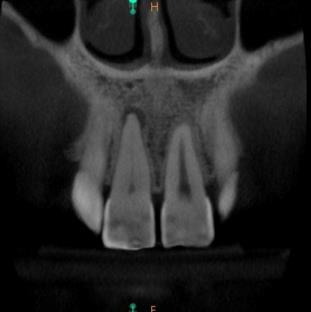

Poniższe zdjęcie przedstawia: